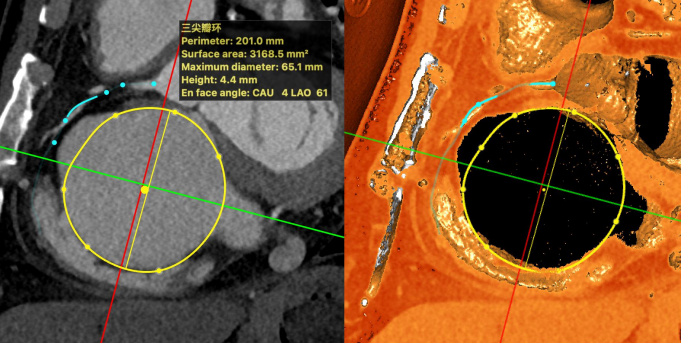

CTA Assessment:

- Tricuspid annulus circumference: 20.1cm, area: 31.7cm² (massive tricuspid annulus);

- Septal-lateral diameter: 63mm, antero-posterior diameter: 63mm;

- RCA: Closest distance to coronary artery measured during systole approximately 8.9mm. Left dominant type, distal right coronary artery not visualized;

- Optimal fluoroscopic projection: Tricuspid short axis CAU8LAO60.